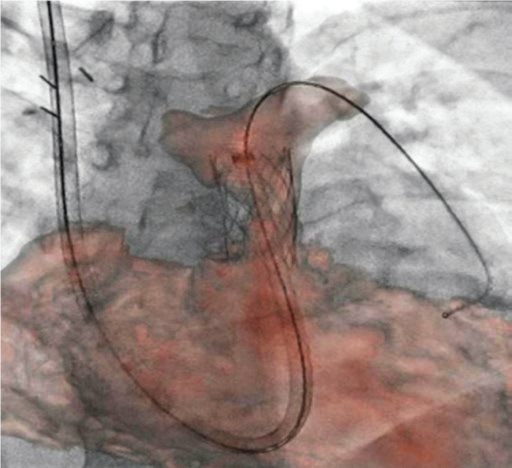

Програмне забезпечення MM Roadmap (або Multi-modality fusion) забезпечує додаткову інформацію завдяки 3D-візуалізації судинної анатомії, що успішно використовується при плануванні та навігації транскатетерної заміни клапану для лікування вроджених вад серця.

MM Roadmap дозволяє суміщувати 2D-флюороскопічні зображення з раніше отриманим 3D-об’ємом. Це може бути КТ або МРТ об’єм при чому незалежно від виробника сканера, або з ангіографічної системи Canon.

Суміщене зображення на моніторі змінюватиметься синхронно в залежності від нахилу С-арки, зміни SID, поля огляду, висоти та положення деки столу.

Можливість використання програмного забезпечення MM Roadmap під час складних втручань допомогає скоротити тривалість опромінення та об’єм введеної контрастної речовини..